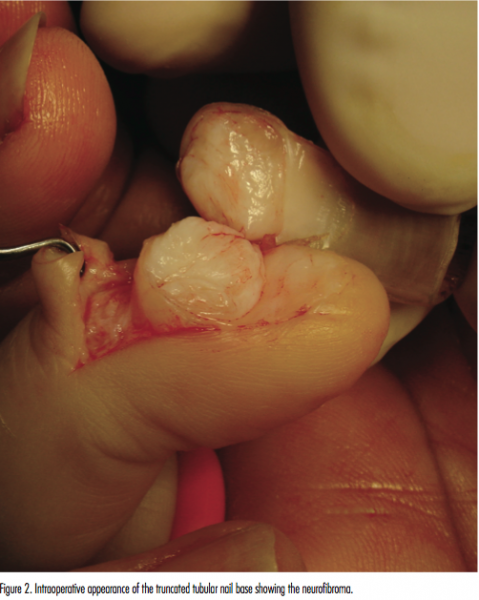

There was no family history of neurofibromatosis type 1 in our patient. On examination, the nail had a tubular shape with a very thin dorsal nail plate and a thick deep nail plate (Figures 1A-C). The undersurface of the nail appeared to be attached to the nail bed, with the nail tissue growing into the hollow tube. The nail near the origin of the growth appeared to be thin to a point where the soft tissue below could be seen. No other signs of neurofibromatosis type 1, such as café-au-lait spots, axillary freckling, or Lisch nodules were noted on examination. An initial x-ray showed no evidence of bony involvement. Elective surgery was then performed. Two axial nail incisions in the nail fold elevating the eponychium allowed exposure of a soft fleshy white dense mass originating from the nail germinal and sterile matrix (Figure 2). This mass was excised flush with the nail bed. Histologic examination confirmed the diagnosis of a solitary subungual neurofibroma. Healing and regrowth of the nail were uneventful on follow-up visits. There was no tumor recurrence at 6 months following surgery.